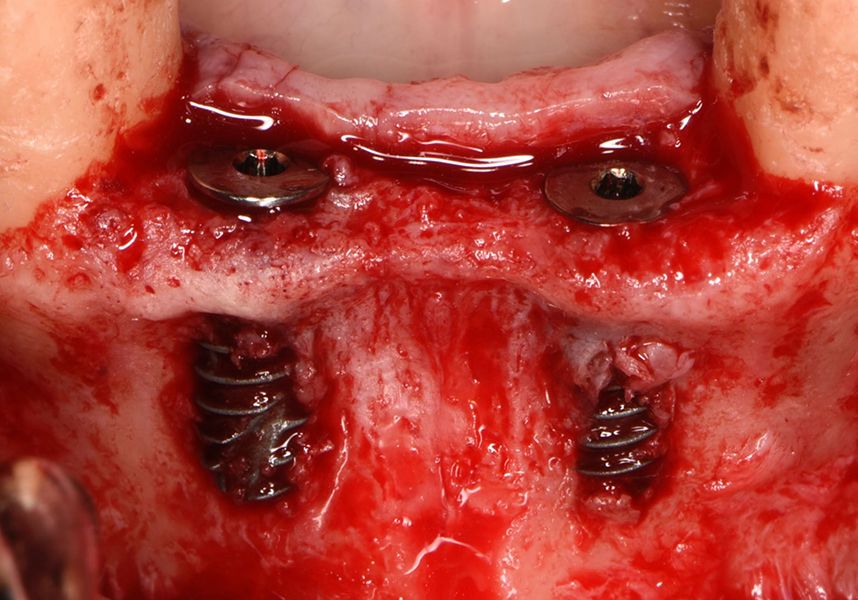

To treat the defect, bone regeneration was carried out simultaneous to the surgical process, with an autologous bone graft from the patient. In the internal part of the graft we used autologous cortical bone obtained by scraping (Safescraper) and from the biological drilling, at low revolutions and without irrigation, from the other implant beds. In the external layer of the regeneration we used a xenograft (Genoss, Osteogenos) and this was covered with a reabsorbable collagen barrier membrane (Evolution STD, Osteogenos).

The membrane was sutured with PGA reabsorbable suture to the periosteum to secure it, thus avoiding subsequent reentry to remove fixings such as tacks.

In the posterior sector three Biomimetic Ocean IC implants of 4.0x10 were inserted in positions 36, 34 and 46 with delayed load. A small regeneration was also carried out with autologous bone in the implant in position 34, where there was no exposure, but the vestibular cortical was very fine after implant insertion.